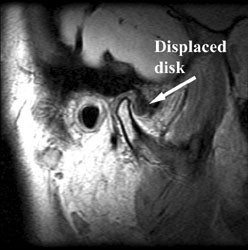

The TMJ can cause problems if the disk gets displaced from it's normal position on top of the mandibular condyle.

Symptoms and imaging: Clinical symptoms are often pain, clicking, locking, and limitation of opening. The best imaging technique to study the TMJ is MR imaging. MR demonstrates the bone and the soft tissue, and especially the disk can be seen. TMJ MR imaging is totally noninvasive and requires no injections.

MR Imaging